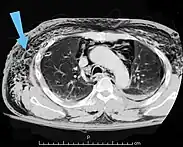

![]() | |

| An abdominal CT scan of a patient with subcutaneous emphysema (arrows) | |

Significant cases of subcutaneous emphysema are easy to diagnose because of the characteristic signs of the condition.[1] In some cases, the signs are subtle, making diagnosis more difficult.[13] Medical imaging is used to diagnose the condition or confirm a diagnosis made using clinical signs. On a chest radiograph, subcutaneous emphysema may be seen as radiolucent striations in the pattern expected from the pectoralis major muscle group. Air in the subcutaneous tissues may interfere with radiography of the chest, potentially obscuring serious conditions such as pneumothorax.[18] It can also reduce the effectiveness of chest ultrasound.[27] On the other hand, since subcutaneous emphysema may become apparent in chest X-rays before a pneumothorax does, its presence may be used to infer that of the latter injury.[13] Subcutaneous emphysema can also be seen in CT scans, with the air pockets appearing as dark areas. CT scanning is so sensitive that it commonly makes it possible to find the exact spot from which air is entering the soft tissues.[13] In 1944, M.T. Macklin and C.C. Macklin published further insights into the pathophysiology of spontaneous Macklin's Syndrome occurring as a result of a severe asthmatic attack.